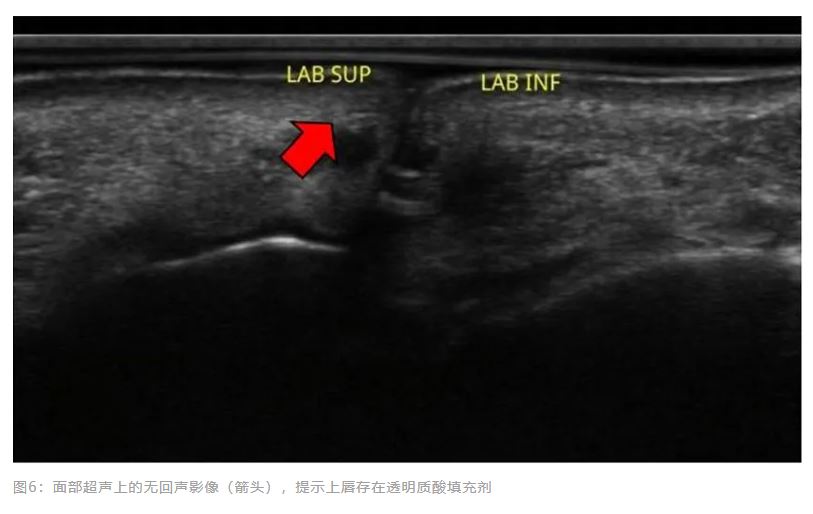

、全景X光片和面部超声检查。初步处方了甾体抗炎药。血常规、尿常规和全景X光片未显示任何可以解释水肿过程的变化。超声检查显示上唇和下唇有无回声影像,具有透明质酸沉积的特征,表明诊断为持续性和间歇性迟发性肿胀。

在最后一次低水平激光治疗一个月后,进行了新的面部超声检查,该检查同样显示有无回声影像提示透明质酸存在,但仅在上唇(图6)。